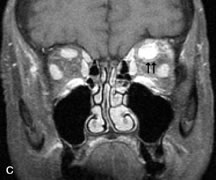

PATIENT PREPARATION Before MRI is performed, patients must be screened and prepared to avoid the potential hazards associated with the strong magnetic field. Patients who have ferrous aneurysm clips or cardiac pacemakers, who depend on life-support equipment, or who retain a possible metallic intraocular foreign body are not candidates for this imaging modality. MRI cannot be performed on obese patients who cannot fit into the bore of the magnet. Patients who are claustrophobic may not tolerate a prolonged period of study within the confines of the magnet, whereas others might do well if given a mild sedative. All worn metallic objects (e.g., necklaces, watches) should be taken off, credit cards set aside, and eye makeup removed before entering the room containing the magnet.5,20,34,35,36 NORMAL ORBITAL ANATOMY T1-weighted images provide the best anatomic details of the orbit because they display superior contrast resolution between normal structures (see Fig. 8). The vitreous has a long T1, resulting in an intermediate signal similar to brain, whereas the crystalline lens and sclera appear dark because of a longer T1 and short T2. The extraocular muscles, like all skeletal muscles, demonstrate a moderately long T1 and short T2 and highly contrast with the intense signal of the surrounding orbital fat (adipose tissue has an extremely short T1). The lacrimal glands appear as mottled areas of reduced intensity of the signal from the orbital fat in the lacrimal fossa. The optic nerves are seen with the same signal intensity as brain white matter and are hypointense relative to the orbital fat because their Tl is longer than the Tl of fat but shorter than the Tl of water. Cortical bone is not well delineated because it contains little free water, yielding minimal signal in MRI, and thus appears dark on all pulse sequences. This feature explains why MR images of the orbital apex and intracanalicular portion of the optic nerves are superior to comparable CT scans. Partial volume averaging of the bones in these regions obscures soft tissue details on CT images, whereas MRI reveals the signals only from the soft tissue structures with no cortical bone input. Bone marrow, on the other hand, is seen as a relatively intense signal because of its high fat content (see Fig. 8).37,38 T2-weighted pulse sequences are not ideal for imaging normal anatomy; however, they are particularly useful in revealing pathologic conditions (see Fig. 9). T2-weighted studies are most easily recognized by a bright vitreous signal. ORBITAL DISEASES Vascular Lesions Cavernous hemangiomas appear as well-circumscribed, smooth, usually intraconal masses that are isointense to muscle on T1-weighted images and hyperintense on T2-weighted images (Fig. 12). Patchy early enhancement is typically followed by diffuse, more homogeneous enhancement.39 The internal architecture of the mass, including septation and internal vasculature, may often be appreciated with high-quality orbital imaging.40 Lymphangiomas consist of ectatic vascular channels within a connective tissue stoma with varying degrees of lymphoid cellularity. On MRI, these tumors are typically poorly circumscribed, multicompartmental, and heterogeneous, often showing cystic dilations with fluid levels (Fig. 13). The signal characteristics within lymphangiomas vary considerably, reflecting cystic and solid components and the varying paramagnetic characteristics of blood at different stages of degradation.40–42 Acute hemorrhage appears hypointense on both T1- and T2-weighted formats. Methemoglobin present in subacute hemorrhage (3 to 14 days) leads to hyperintense signal on both T1- and T2-weighted images.41 A small percentage of lymphangiomas appear radiologically indistinct from orbital cavernous hemangiomas.43 Orbital varices are venous malformations that expand with increased systemic venous pressure, such as with Valsalva maneuvers. Because rapid acquisition of images during a Valsalva maneuver is important in imaging such a lesion, conventional or spiral CT is currently the modality of choice.44 MRI is an excellent modality for demonstrating enlargement of the cavernous sinus and dilation of the superior ophthalmic vein in patients with high-flow carotid-cavernous fistulas (Fig. 14).37MRA may be helpful in the evaluation of the venous outflow pattern. The rapidly flowing blood in these vascular structures carries the excited protons out of the section before they can be imaged, resulting in their dark appearance.5 In low-flow dural arteriovenous malformations, MRA may help define the arterial feeding vessels.45 Neural Lesions MRI is more effective than CT in delineating the intracranial optic nerves, chiasm, and optic tracts and, for this reason, is the preferred imaging modality in the evaluation of optic nerve disorders. The spatial relationships and image contrast of the orbital tissues with intraorbital optic nerve tumors is comparable between the two imaging modalities. The normal nerve is isointense to brain and appears enlarged and kinked owing to infiltration of an optic nerve glioma on T1-weighted images. Gliomas appear hyperintense on T2-weighted images and may be heterogeneous owing to cystic areas within the tumor. Contrast enhancement is variable.46 Intraorbital and intracranial optic nerve sheath meningiomas are usually isointense to cortical gray matter on Tl-weighted images and remain isointense on proton density studies (Fig. 15). Gd-DTPA is useful in delineating the intracranial extension of optic nerve meningiomas.7,47 The hyperostosis of bone and calcification associated with meningiomas are not demonstrated as well on MRI studies as on CT scans.20,37 Gd-DTPA–enhanced MRI also appears promising in the study of the permeability of the blood–brain barrier in selected optic neuropathies.22,48 MRI may reveal an enlarged optic nerve and some degree of contrast enhancement in cases of optic neuritis.49 Muscle Disorders Extraocular muscle enlargement in patients with thyroid-associated orbitopathy is demonstrated equally well with CT and MRI studies. However, the superior tissue contrast on MR images reveals better details of the relationships of the optic nerve to the thickened muscles at the orbital apex (Fig. 16).50 In addition, MRI may be able to differentiate between muscles that are enlarged as a result of edema and active inflammation and those enlarged because of fibrosis by their T2 relaxation times.21 Quantitative MRI was not found to be accurate in predicting the success of low-dose orbital irradiation.51 However, a muscular index relating the diameters of the rectus muscles to the bony orbital dimensions was useful in predicting optic nerve compression.52 MRI is also effective in imaging orbital tumors of mesenchymal origin, such as rhabdomyosarcoma, particularly in the assessment of extension into the anterior and middle cranial fossae (Fig. 17).37 The lack of any pathognomonic radiologic features necessitates rapid orbital biopsy when rhabdomyosarcoma is suspected. Osseous Lesions In general, CT is the imaging modality of choice when details of quantity and quality of bone are needed; however, abnormalities of bones can be detected indirectly by MRI. Cortical bone appears black (signal void) on MR images because of its low proton density and free-water content. The absence or discontinuity of the signal void of the orbital walls may represent bony destruction or fracture. Hyperostosis associated with prostate metastases or meningioma is visualized as areas of black smudging.50,53 Diseases in which the bone is replaced by pathologic tissues with a high free-water content, such as fibrous dysplasia, are well demonstrated on MRI. An intermediate signal intensity on T1-weighted images and hypointense signal on T2-weighted images is representative of fibrous dysplasia. Enhancement on post–Gd-DTPA MR scans is seen and is more evident in areas that are less mineralized.54 Cystic Lesions Dermoid cysts appear as rounded, well-defined lesions typically contiguous with an orbital bony suture. The high-intensity signal on T1-weighted images is attributed to the sebaceous-produced lipid contents (Fig. 18).31,50 Mucoceles may demonstrate a hypointense or hyperintense signal on MR images, depending on the concentration of proteinaceous or inflammatory fluid components. The integrity of the bony walls of the expanded sinus cavities cannot be assessed on MR as well as by CT.37,50,55,56 A high-signal intensity on Tl- and T2-weighted images is characteristic of orbital chronic hematic cysts because of the blood-breakdown products within the cysts.57 Trauma Although soft tissue relationships are usually better demonstrated on MRI, the evaluation of craniofacial bony trauma is preferable with CT. For example, prolapse of orbital fat through a fracture site and hemorrhage of adjacent tissues are demonstrated in an MR image, but the actual fractured bone is not imaged. Three-dimensional MRI of the orbit in subacute trauma has been described,58 although its precise role is not currently established. MRI has been suggested to be superior to CT in detecting intraorbital wooden foreign bodies.59,60 In a series of penetrating orbital injuries with organic foreign bodies, however, MRI was able to identify the foreign body in only four of seven cases.61 With an in vitro model for wood foreign body, McGuckin and colleagues concluded that CT was the imaging modality of choice.62 A careful history and, in selected cases, plain films to rule out a metallic foreign body are crucial before MRI is considered in patients with periocular trauma. MRI is particularly helpful in the detection and characterization of subperiosteal hematomas of the orbit (Fig. 19). They are most commonly seen in the subperiosteal space of the superior orbit as well-defined masses following a traumatic injury. The signal intensity varies depending on the acute, subacute, or chronic nature of the hematoma, based on the stage of blood degradation. Fresh hemorrhages are hypointense on T1-weighted images and hyperintense on T2 images. Hematomas that are 1 to 7 days old are hypointense on both T1- and T2-weighted images. T1-weighted images of hematomas more than a week old are hyperintense due to the oxidation of deoxyhemoglobin to methemoglobin, whereas the T2 images remain hypointense.63 Metastatic Tumors Breast carcinoma metastatic to the orbit has been demonstrated to be hypointense to the surrounding orbital fat on T1-weighted studies and hyperintense on T2-weighted images and has an affinity to the extraocular muscles (Fig. 20).50,64 The MRI characteristics of prostate carcinoma metastatic to the orbit have been described as involving the greater and lesser wing of the sphenoid, orbital roof, and optic canal. Diffuse bone hypertrophy with isointense or slightly hyperintense tissue on T1-weighted images represents the osteoblastic carcinomatous bone infiltration. Contrast enhancement is variable on T1-weighted and fat-suppressed images.65 Most other metastatic tumors also have a lower intensity signal on T1-weighted images and appear to displace or infiltrate normal orbital structures; however, their signal characteristics are variable on T2-weighted MR images.66 Many metastatic tumors demonstrate bright contrast enhancement with Gd-DTPA. Infectious Disorders MRI findings of preseptal and orbital cellulitis typically include increased signal intensities on T2-weighted images of the eyelids and orbital fat, respectively, due to the increased water content of the tissues. Since most cases of bacterial orbital cellulitis are associated with paranasal sinusitis, hyperintense signals of the affected sinuses may also be found on T2-weighted images as well as enhancement of polyps and granulation tissue on postgadolinium T1-weighted MR images. Subperiosteal abscess formation may occur due to contiguous spread of infection from the paranasal sinuses and appear on MRI as an area of intermediate signal on T1-weighted and proton-weighted MR images. The abscess may appear slightly hyperintense compared with muscle on T2-weighted scans with the necrotic contents having the greatest intensity.67 MRI and MRV are more sensitive than CT in revealing cavernous sinus thrombosis. Engorgement of the cavernous sinus, extraocular muscles, and ophthalmic veins is seen with hyperintensity of the thrombosed sinuses evident on all pulse sequences. The enlarged, thrombosed superior ophthalmic vein appears less hypointense than the normal contralateral ophthalmic vein, and hyperintensity within the lumen of the vessel may be seen on T1- and T2-weighted MR images.68 Inflammatory and Lymphoproliferative Lesions Inflammatory conditions of the orbit, both idiopathic (inflammatory pseudotumor) and those of known causes, have been found to be hypointense to fat and isointense to muscle on Tl-weighted studies and isointense or slightly hyperintense to fat on T2-weighted images (Fig. 21).50,64,69 The more fibrous or sclerosing varieties have less signal intensity on T2-weighted images. Marked enhancement is seen in pseudotumor infiltrates after gadolinium administration.70 The same signal characteristics are demonstrated in patients with Tolosa-Hunt syndrome, with mass lesions seen in the cavernous sinuses and orbital apices.71 Lymphomas have MRI characteristics similar to those of inflammatory lesions in that they are hypointense to fat and isointense to muscle on T1-weighted images (Fig. 22). They may appear hyperintense to fat on T2-weighted images, perhaps owing to less fibrosis than that seen in orbital inflammatory pseudotumor, although this is not a consistent finding.31,50,66 Lymphoid tumors typically enhance moderately after contrast injection. Unfortunately, studies have shown that tumor density and homogeneity are similar between inflammatory and malignant orbital infiltrates, and MRI cannot differentiate these lesions.72,73 Lacrimal Gland Tumors Lacrimal gland lesions present special problems in diagnosis and management. Pleomorphic adenoma (benign mixed tumor) should not be biopsied, but rather excised in toto. On the other hand, for lymphoma and inflammatory infiltrates, incisional biopsy is more appropriate than complete excision of the lacrimal gland. Thus, preoperative clinical and radiologic evaluation are especially crucial in planning appropriate surgical management. Pleomorphic adenomas demonstrate long T1 and T2 signal characteristics. They may show heterogeneity on T2-weighted images74 and moderate to marked enhancement with contrast.75 Signal characteristics of adenoid cystic carcinoma include hypointensity to fat on T1-weighted images, hyperintensity to fat with increased T2 weighting, and isointensity to fat on proton density-weighted studies (Fig. 23).31,75 Secondary bony alterations of the lacrimal fossa associated with lacrimal gland tumors, such as remodeling (benign mixed tumor) or destruction (adenoid cystic carcinoma), are seen indirectly on MR images; however, bone windows on CT scans provide better delineation of these changes. In contrast to the round or globular appearance of benign or malignant epithelial tumors of the lacrimal gland, lymphoproliferative tumors usually appear to be molding or draping onto the globe and the surrounding bony orbit. LACRIMAL DRAINAGE SYSTEM DISORDERS MRI with surface coils provides excellent spatial resolution and tissue-specific signal intensities of the lacrimal drainage system. These parameters have been found useful to more accurately demonstrate the extent of lesions in the lacrimal sac and differentiate long-standing mucoceles from solid tumors than CT.76 Physiologic studies in patients with tearing disorders now include MR dacryocystography, in which Gd-DTPA is either placed topically in the conjunctival fornix or injected by cannulation into the lacrimal sac. They provide a detailed morphologic and functional analysis of the lacrimal excretory system; however, they are no more sensitive than digital-subtraction dacryocystography or CT dacryocystography.77–79 INTRAOCULAR TUMORS On MRI, uveal melanomas have a typical appearance that helps to differentiate them from other primary and secondary intraocular tumors as well as choroidal detachments. Pigmented melanomas are hyperintense on Tl-weighted images, hypointense on T2-weighted studies, and hyperintense on proton density–weighted examinations (Fig. 24).30,31,50,80–82 These signal characteristics have been attributed to the paramagnetic properties of melanin because of stable free radicals that shorten the T1 and T2 relaxation times. Moderate enhancement is seen on postgadolinium T2-weighted images. Gadolinium-enhanced T1-weighted images are particularly sensitive in detecting choroidal melanomas.83 MRI may be less sensitive in detecting extrascleral extension of tumor than echography performed by an experienced ultrasonographer.84 Tumors metastatic to the choroid are hyperintense on T1- and T2-weighted images.24 The signal characteristics, however, may be similar to those seen with choroidal melanoma. Choroidal hemangiomas, on the other hand, have an intermediate signal on T1-weighted sequences and become hyperintense on T2-weighted images50 as well as proton density–weighted images.81 Retinoblastomas display moderate signal intensity on T1-weighted studies and a low signal on T2-weighted images.31,80,85 Calcification can be easily detected by CT and ocular ultrasonography but is not imaged by MRI.25,50 The presence of optic nerve involvement is best evaluated by MRI. ACQUIRED ANOPHTHALMIA When an eye is removed owing to tumor or trauma, an implant is typically placed in the intraconal space. MRI may be useful in defining the size, shape, and position of such orbital implants.86 Porous hydroxyapatite or polyethylene implants are preferred by many surgeons performing enucleation or evisceration. A porous implant offers the possibility of supporting a motility coupling peg to increase the movement of the overlying prosthesis. MRI with contrast is used by some surgeons to evaluate the degree of fibrovascular ingrowth in hydroxyapatite87 and porous polyethylene88 implants prior to motility peg placement. |